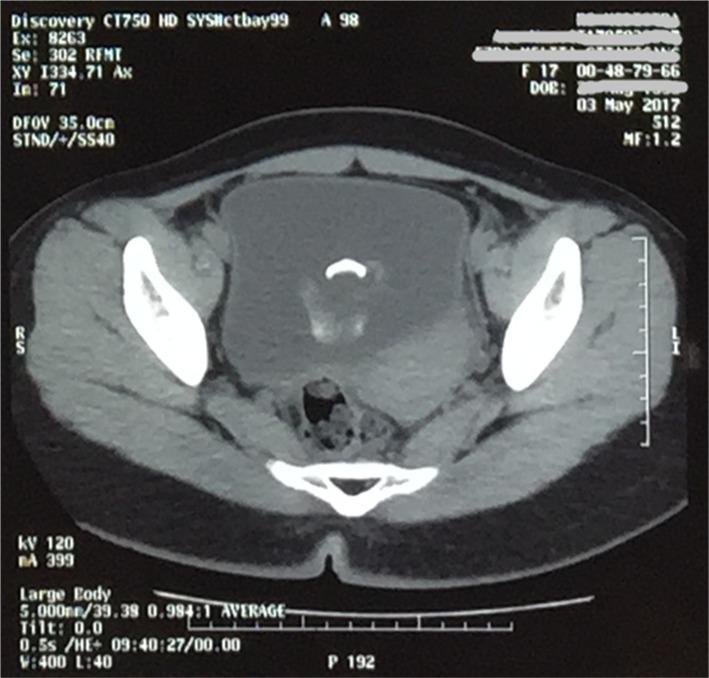

A very rare case of teratoma of the bladder in a 17-year old Asian girl is presented. The patient had chief complaints of hematuria. The diagnosis was made on cystoscopy and confirmed histopathologically. Complete excision was possible. To the authors' knowledge, this is the first such case reported from Indonesia and the South East Asian region.

A bladder teratoma mimics the presentation of a bladder stone, clinically and radiologically. A dermoid cyst should be considered as a differential diagnosis, especially when the stone appears to be confined to the bladder wall during examination.